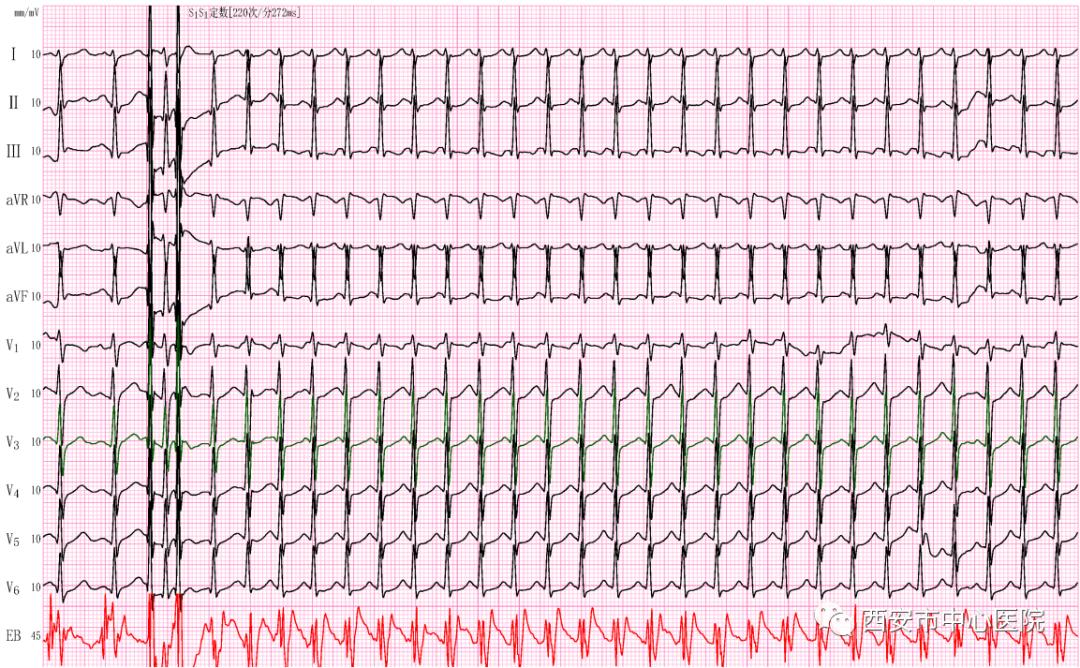

莫女士,48岁,夜间突发心慌1小时来我科,该女士既往曾出现过突然发作的心慌、胸闷,发作时间短,能很快好转,发作不频繁,未引起重视。最近两年上述症状发作后持续时间更长,各种刺激迷走神经的办法不能自行终止。 心电图检查:心室率214次/分,诊断“阵发性室上性心动过速”,为了尽快解除患者痛苦,我们准备给患者进行一场无创的心脏电活动检查及心动过速的“刹车”治疗。

首先,从莫女士的鼻腔插入食道电极导管到达心脏位置,接入相应的导联,记录到如图2所示的体表心电图和食道心电图(图中红色部分)。通过食道心电图高大清晰的P波以及心房和心室的关系,我们可以明确莫女士的心动过速是因为心脏除了心房心室之间的正常的传导通路(房室结)外,在心脏左侧壁比别人多了一条“电路”(隐匿性旁路),如同我们生活中私接乱拉了一路电线,就是这条多余的“电路”引起患者心跳增快,心慌、胸闷不适。莫女士的心律失常是“顺向型房室折返性心动过速”。

(图2)

我们通过食管电极发放数个低能量的电刺激(食道调搏),心跳从214次/分的顺向型房室折返性心动过速转换到109次/分的窦性心律(图3),患者痛苦的表情立刻消失。

(图3)